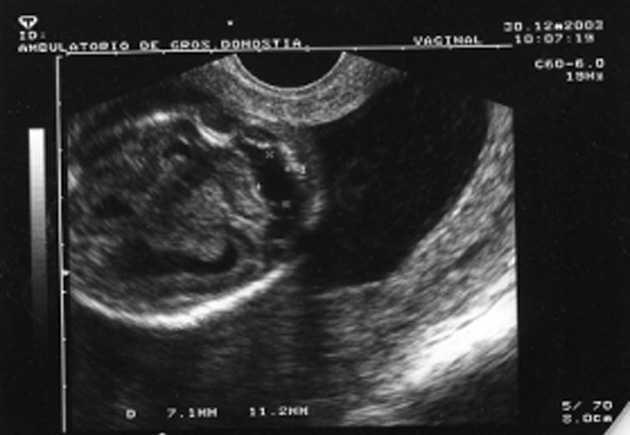

Al cabo de una semana se repite la ecografía, con los siguientes hallazgos: frecuencia cardíaca fetal (FCF) positiva; feto en posición cefálica; sexo masculino. peso fetal en percentil 10-25; aumento generalizado del espacio subaracnoideo, con aspecto de parénquima encefálico de pequeño tamaño y con escasas circunvoluciones; se observa comunicación entre las astas anteriores de los ventrículos laterales; cerebelo de morfología anómala con ausencia parcial de vérmix cerebeloso y cisterna magna límite; notable hiperecogenicidad intestinal; líquido amniótico normal. El diagnóstico fue: variante de Dandy-Walker + aumento de espacio subaracnoideo + holoprosencefalia lobar + hiperrefringencia intestinal (figs. 1 y 2).

Figura 1.Variante de Dandy-Walker: quiste en fosa posterior, agenesia parcial de vermis cerebeloso, IV ventrículo normal o mínimamente agrandado.

-- Variante de Dandy-Walker: quiste en la fosa posterior y defecto parcial del vermis cerebeloso. En este caso no se visualizó el aumento de los ventrículos laterales por ecografía, que luego sí fue observado en la necropsia.